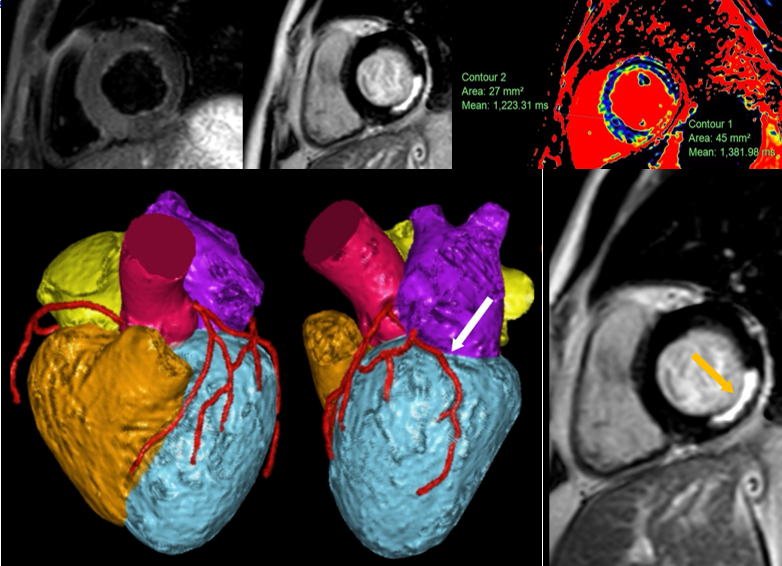

重医附一院放射科(金山院区)陶黎副主任技师在增强扫描中发现异常情况,患者心肌T1值异常升高、室壁呈现特征性强化。这是心脏发出的求救信号,代表的是回旋支血管的缺血。医疗团队立即启动绿色通道,同时加做冠状动脉MRA方便精准定位。

当5分钟后,血管影像浮现——闭塞血管位置清晰显示。同时马上通知介入手术团队定制手术方案。

这场教科书式的接力救治,源于冠状动脉MRA结合心脏MR的多参数成像,可以一次检查完成从血管病变到心脏结构功能、心肌组织特性和血流的“一站式”影像评估,这种无辐射的“全息扫描”,让医生同时掌握血管形态、心肌活性、心脏功能三大情况。

冠状动脉磁共振血管成像技术(MRCA)是应用MR获得冠状动脉图像以观察血管解剖形态的成像技术,可用于发现管腔狭窄、扩张及管壁异常等病变。目前重庆医科大学附属第一医院放射科(金山院区)团队将3D_mDIXON_WH血管成像技术应用在MRCA检查中。